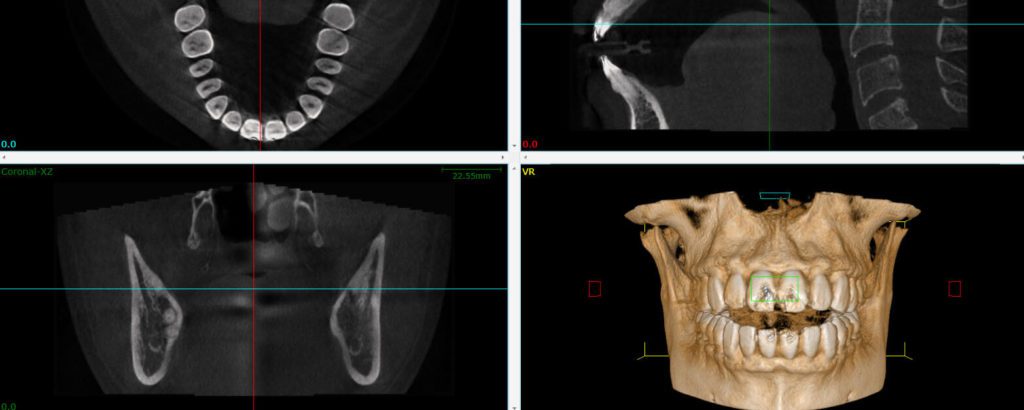

If you’re considering dental implants you may have been surprised to learn that the procedure is not always possible without some dental work to prepare the mouth. Many patients who are considering dental implants learn that in order to support the implant they must first have a bone grafting procedure performed. Dr. Terry Vines of […]